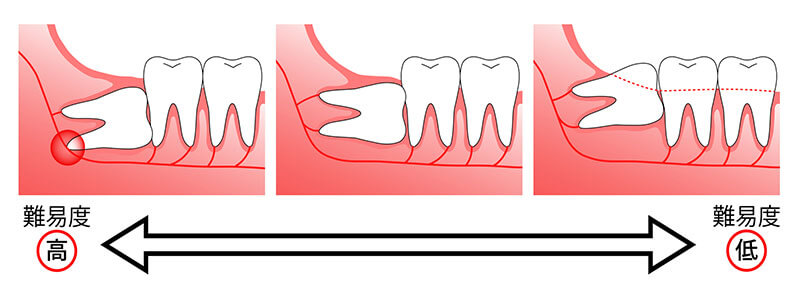

「親知らずをそのまま残しておいても大丈夫ですか?」という質問をよく受けます。正常に生えている場合は残すことも可能です。ただ、歯ブラシで磨きにくい親知らずは虫歯になり易く、不自然(斜めや横に寝ている状態)に生えている場合とあわせて、当院では痛みや虫歯が出来ないうちに抜歯されることをお勧めしています。

「親知らずをそのまま残しておいても大丈夫ですか?」という質問をよく受けます。正常に生えている場合は残すことも可能です。ただ、歯ブラシで磨きにくい親知らずは虫歯になり易く、不自然(斜めや横に寝ている状態)に生えている場合とあわせて、当院では痛みや虫歯が出来ないうちに抜歯されることをお勧めしています。

基本は抜歯になります。親知らずが正常に生えている場合は残すこともありますが、不完全に生えている方が多いです。

親知らずは虫歯以外にも多くの症状を引き起こすため、10代中ごろに親知らずを抜くことをおすすめします。この時期に抜歯することにより、多くの利点があります。